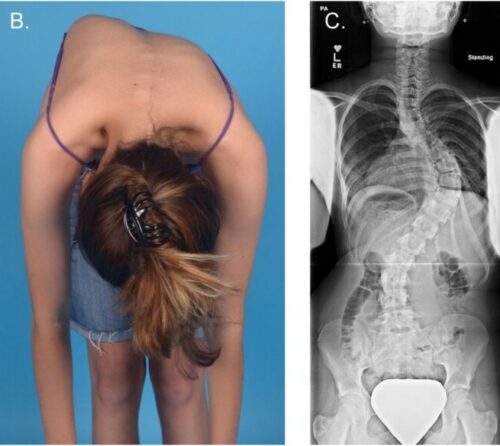

اعوجاج العمود الفقري، أو الجنف، هو انحناء جانبي غير طبيعي للعمود الفقري يمكن أن يظهر في مرحلة الطفولة أو المراهقة. غالبًا ما يكون الانحناء بسيطًا في البداية ولا يسبب ألمًا، لكن مع مرور الوقت وبدون متابعة، قد يتفاقم ويؤثر على شكل الجسم ووضعية العمود الفقري.

إذا لاحظتِ علامات انحناء في ظهر طفلك، أو لاحظتِ عدم تماثل بين الجانبين، فلا تتردد الأن في استشارة مجانيه من طبيب متخصص.

الأهالي يجب أن يكونوا يقظين إذا لاحظوا أي من الأعراض التالية:

• زيادة مفاجئة في زاوية الانحناء للعمود الفقري.

وجود أي من هذه العلامات يستدعي تقييم طبي شامل، يشمل طبيب عظام وأحيانًا طبيب أعصاب، للتأكد من سلامة العمود الفقري والجهاز العصبي.

زيارة طبيب العظام كل 3–6 أشهر، وإجراء الأشعة لمتابعة زاوية الانحناء.